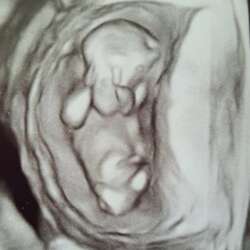

Ik heb een echo bij de gynaecoloog gehad. Daar waren heel veel follikels in m’n ene eierstok te zien. Dat kan wijzen op pcos. Daarnaast hebben ze nog onderzoek gedaan naar mijn suiker en naar m’n bloed gekeken. Ten tijde van het bloedonderzoek had ik een spiraal, dus dat had weinig nut :/. Bij de gynaecoloog was het eigenlijk een nare ervaring, want ze wilden mijn spiraal niet verwijderen als ik niet morgen wilde beginnen aan kinderen, zeg maar. De huisarts heeft m’n spiraal toen verwijderd.